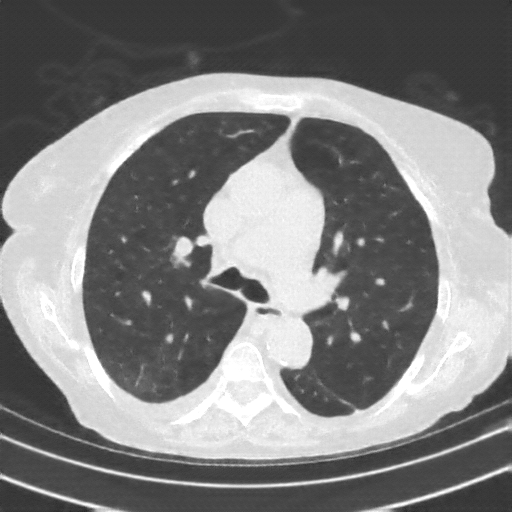

Original NATIVE CT scan (input)

Full window (WL 1023.5, WW 4095 β†’ Low βˆ’1024, High +3071)

Lung window (WL -600, WW 1500 β†’ Low βˆ’1350, High +150)